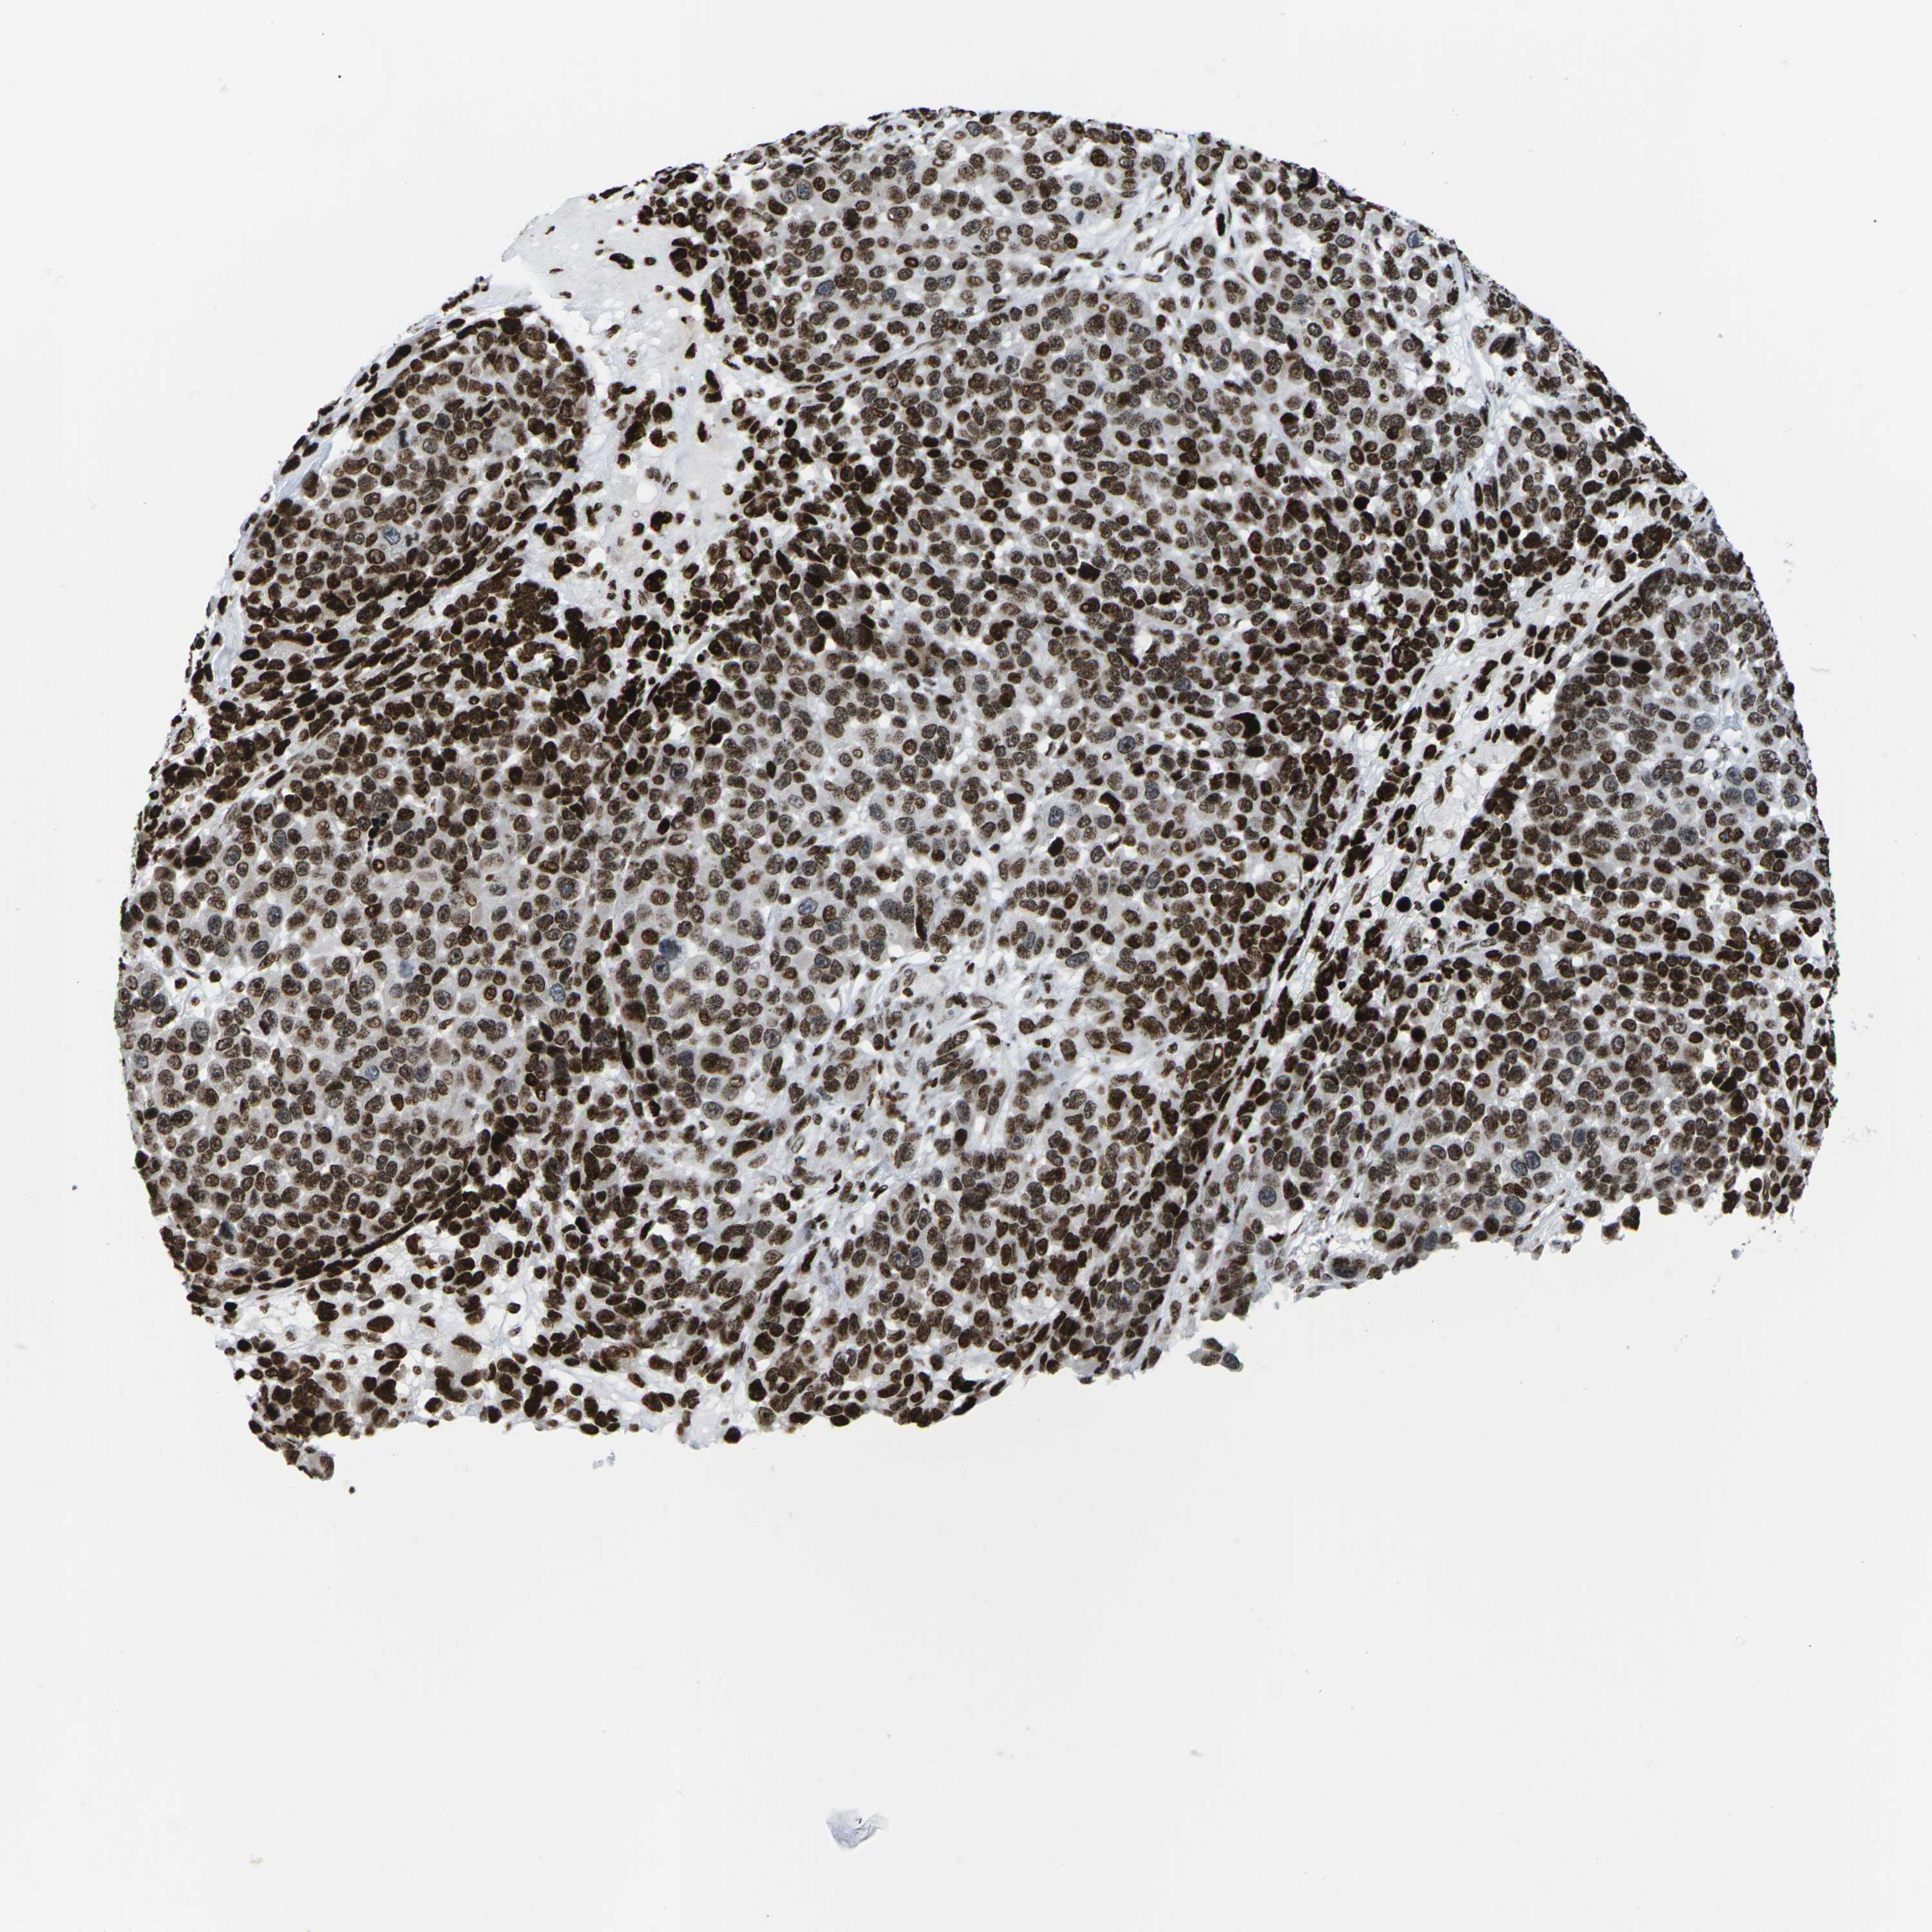

MELANOMA - Protein expressioni

A mouse-over function shows sample information and annotation data. Click on an image to view it in a full screen mode. Samples can be filtered based on level of antibody staining by selecting one or several of the following categories: high, medium, low and not detected. The assay and annotation is described here.

Note that samples used for immunohistochemistry by the Human Protein Atlas do not correspond to samples in the TCGA dataset.

Antibody stainingi

Antibody staining in the annotated cell types in the current human tissue is reported as not detected, low, medium, or high, based on conventional immunohistochemistry profiling in selected tissues. This score is based on the combination of the staining intensity and fraction of stained cells.

Each image is clickable and will lead to virtual microscopy that enables deeper exploration of all samples and also displays staining intensity scores, fraction scores and subcellular localization as well as patient and tissue information for each sample.

Antibody HPA055907

Antibody CAB011506

Staining

High

Medium

Low

Not detected

Intensity

Strong

Moderate

Weak

Negative

Quantity

>75%

75%-25%

<25%

None

Location

Nuclear

Cytoplasmic/membranous

Cytoplasmic/membranous,nuclear

Malignant melanoma, NOS

Malignant melanoma, Metastatic site